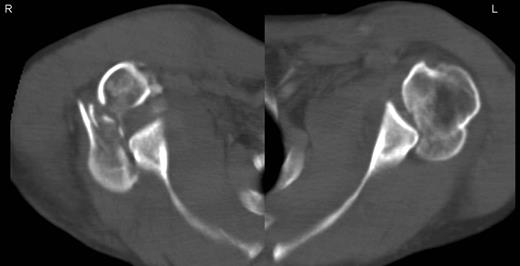

A 48-year-old patient was referred to a level I trauma center after the first incidence of an epileptic convulsion. The patient was alert and oriented with retrograde amnesia from the time of convulsion. Peripheral neurology was normal. The X-rays showed bilateral posterior shoulder dislocation with fractures of both humeral heads (Fig. 1). A CT of the head and both shoulders was performed to exclude intracerebral pathology and to achieve better demonstration of the shoulder fractures (Fig. 2). According to the AO fracture classification, he had a 11-C3.1 fracture on the left side and a 11-C3.3 fracture on the right side. The right side fracture was treated with a cementless hemiarthroplasty (OrTra®, Zimmer, Germany), while an open reduction and internal fixation (ORIF) with an angular stable plate (Philos®, Synthes, Germany) was performed on the left. Despite the high incidence for humeral head necrosis after ORIF in this fracture type, this option was chosen based on the young age of the patient. Postoperative X-rays and CT showed adequate positions of the implants (Fig. 3). The shoulders were immobilized in Gilchrist bandages followed by passive mobilization for the first 6 weeks by physiotherapy with a limitation for abduction and anteversion to 90°. There were no complications intraoperatively or in the first postoperative time. Patient was discharged after 8 days. Antiepileptic therapy was initiated with 5 mg clobazam and subsequent increasing doses over the following weeks. There were no more signs of epilepsy in the follow-up. A CT 4 months after operation showed dislocation of a fragment on the left side which was subsequently resected. At the 1-year postoperative review, the patient showed impingement of the left shoulder with abduction limited to 50° by both the plate and an osteophyte. Radiological assessment revealed signs of necrosis of the head. The plate was removed and the osteophyte resected. Eighteen months after injury, the left shoulder showed progressive avascular osetonecrosis of the head (Fig. 4) and after plate removal an inversed prosthetic replacement had to be performed (Fig. 5). At the last follow-up 3 years after injury, the patient was free of pain with a bilateral range of motion of 90° abduction and elevation.